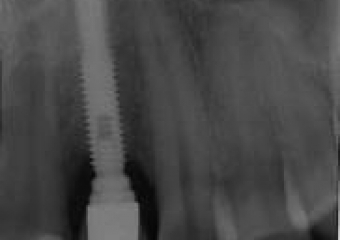

Raio X da primeira prótese fixa